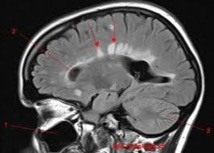

La sclérose en plaques se caractérise par la destruction progressive de la gaine de myéline, qui protège les nerfs du cerveau et de la moelle épinière et joue un rôle essentiel dans la conduction électrique de l'influx nerveux.

Quand cette isolation protectrice est détruite, les impulsions électriques ne peuvent pas circuler efficacement, entraînant des symptômes qui peuvent aller jusqu'à la paralysie ou la cécité.